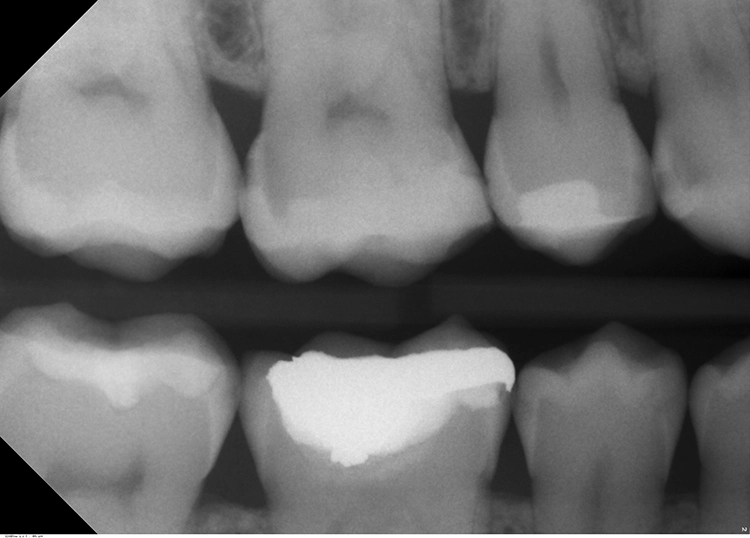

Erst eine weitergehende röntgenologische Untersuchung zeigt das ganze Ausmaß des Kariesbefalls (Abb. 1c). Das Kind wies an fast allen Milchzähnen bereits Dentinkaries, zum Teil auch schon sehr tiefe Läsionen (Zahn 75), auf. Solch ein Befund scheint bei zahlreichen konventionell-restaurativen Maßnahmen bei altersentsprechender mäßiger Kooperation (fast) nur in Narkose behandelbar.

Bei Verdacht auf oder bei bereits bestehender Approximalkaries ist stets eine röntgenologische Untersuchung in Betracht zu ziehen, da eine Approximalkaries selten isoliert auftritt (Abb. 9a) und insbesondere im Milchgebiss durch die vergleichsweise dünne Schmelz-Dentin-Schicht die Nähe vom Defekt zur Pulpa abgeklärt werden sollte (Abb. 9b). Dafür bietet sich die Bissflügelaufnahme an [1], die approximal als Goldstandard in der Kariesdiagnostik gilt.

Dr. J. SchmoeckelDentinkaries zu befunden.

Dr. J. SchmoeckelZudem ist hier die Tiefe der Läsion (Nähe zur Pulpa) gut abschätzbar. Bei der Indikationsstellung für ein Röntgenbild ist immer die zwar geringe, aber dennoch vorhandene Strahlenbelastung zu berücksichtigen [12]. Faseroptische Transillumination (FOTI) Die Kaltlichtsonde bietet sich insbesondere für die erste Untersuchung „scheinbar gesunder“ Approximalflächen an [7], und dies v.a. wenn bereits an einem anderem Zahn eine approximale Läsion oder Füllung detektiert wurde.